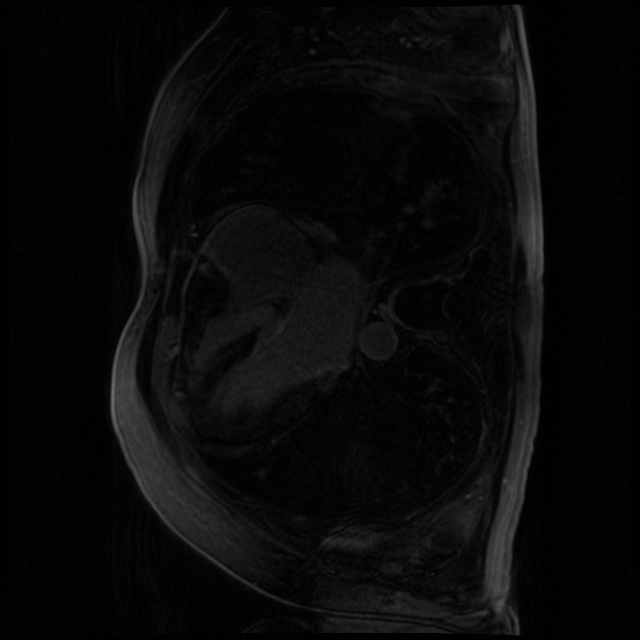

Late gadolinium enhancement magnetic resonance imaging (LGE-MRI) is typically used to provide quantitative information on atrial scars [25]. In this measurement, location and size in the left atrium (LA) indicate pathology (i.e., LA scars) and progression of atrial fibrillation [12].

Nowadays, deep learning models have been widely used to segment LA cavities and quantify LA scars from LGE-MRIs [3] to help radiologists with initial screening for quick pathology detection. Meanwhile, LGE-MRIs are often collected by multiple scanners and possibly in low imaging quality. Each of them produces inconsistent domain information [14], including different contrast and spatial resolutions. (1) Promoting the generalization of a segmentation model against domain inconsistency becomes another challenge.

The LAScarQS dataset includes two tasks: 1). LA and LA Scar segmentation (task 1), and 2). LA Segmentation across scanners (task 2). The first task contains 60 3D LGE-MRIs with labels containing LAs and LA scars, while the second consists of 130 3D LGE-MRIs from multiple medical centers with labels containing only LAs [12].